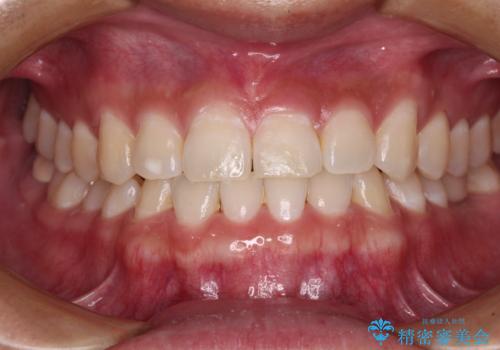

急速拡大とワイヤー抜歯矯正で唇を閉じやすく

- 口元の突出感を気にして来院された患者様です。

デコボコと口元の突出感が認められたため、上下左右の第1小臼歯4本を抜歯してのワイヤー矯正を行うこととしました。

上顎歯列の横幅が狭く、下顎大臼歯の歯軸が舌側に倒れていたため、急速拡大装置により上顎骨を側方に拡大し、咬み合わせを改善することとしました。

上顎歯列幅を拡大したことで、デコボコを容易に解消することができるようになったため、抜歯により得られたスペースを口元の突出感改善に利用することができました。